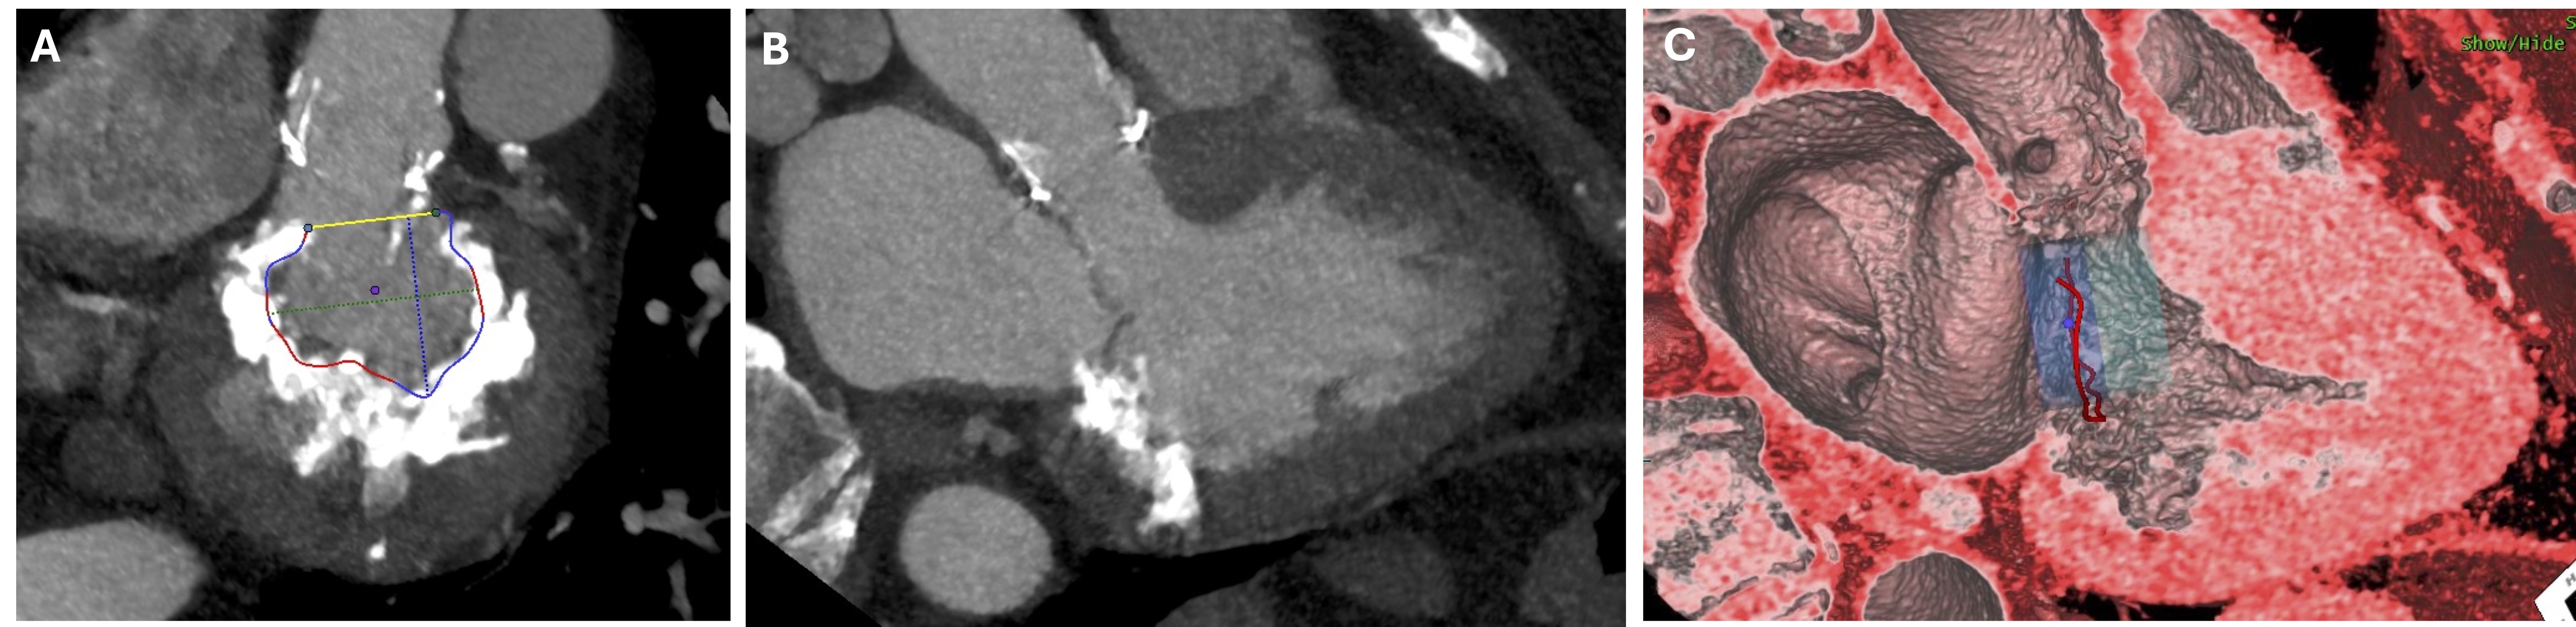

Abstract Body (Do not enter title and authors here): A 71-year-old female with a history of severe aortic stenosis status post aortic valve replacement with a 23mm bioprosthetic valve and aortic root enlargement with bovine pericardial patch 6 years prior, presented with progressive dyspnea and NYHA class III symptoms. Echocardiography revealed preserved left ventricular function and a normally functioning bioprosthetic aortic valve, but severe mitral annular calcification (MAC) with significant mitral stenosis (Mean gradient: 11 mmHg, Mitral valve area: 1.6 cm^2). Cardiac CTA showed severe circumferential MAC with >75% annular involvement and a MAC score of 8. Following multidisciplinary discussion, consensus was reached to proceed with a hybrid open transcatheter mitral valve-in-MAC replacement via right thoracotomy using an atrialized (80% atrial, 20% ventricular) approach to mitigate the risk of LVOT obstruction identified on preprocedural CT planning.

Right femoral cannulation and right anterior thoracotomy were performed. Following the initiation of cardiopulmonary bypass, the pericardium and left atrium were opened. The mitral valve was severely stenotic with extensive calcification involving both leaflets and the annulus, precluding full debridement. Consequently, only a portion of the anterior leaflet was resected to prevent displacement into the left ventricular outflow tract during valve inflation. A balloon-expandable valve was deployed using nominal volume plus 5 mL for optimal expansion and anchoring, aided by atrial sutures and an atrialized cuff. The prosthesis successfully circularized the annulus and was confirmed competent with no evidence of a paravalvular gap or leak.

A hybrid open transcatheter mitral valve-in-MAC procedure offers a viable option for patients unsuitable for conventional surgery or transcatheter approaches. While standard implantation places the valve 2 mm above the annulus (20% atrial, 80% ventricular), we employed an atrialized technique to minimize LVOT obstruction and avoid valve-septal contact. Additional balloon inflation facilitated annular circularization, ensuring full valve expansion and sealing. Meticulous preoperative planning with cardiac CT is essential to guide procedural strategy and optimize outcomes.